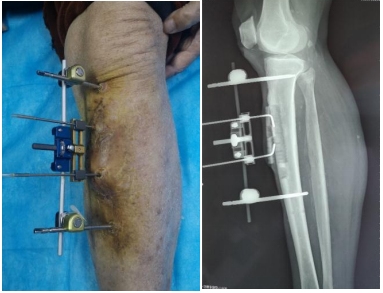

患者男性,86岁,糖尿病足坏疽,动脉硬化闭塞症,心脏支架术后,术前静息痛、冰凉感、麻木症状明显,每天口服6片氨酚双氢可待因片不能缓解疼痛。于2020年10月10日在我院行胫骨横向骨搬移手术。

术后当晚未服用止痛药,第二天足趾末梢皮温34.2C°升至35.9C°